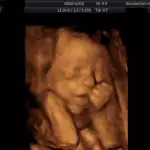

3D/4D ultrazvuk

Tyto fotografie jsou pořízené přístrojem Voluson 730